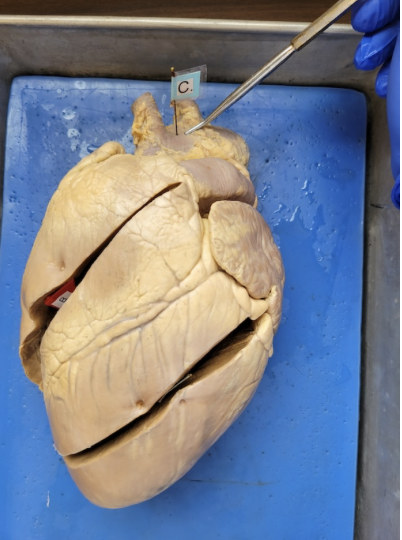

what is this

Aorta